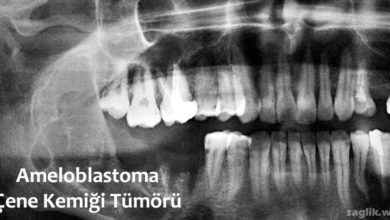

Ameloblastoma Nedir? Belirtileri, Nedenleri, Tedavisi

Ameloblastoma, alt veya üst çene kemiğinde ortaya çıkabilecek nadir, iyi huylu bir kemik tümörüdür. Ameloblastoma, dişlerin koruyucu mine astarını oluşturan…